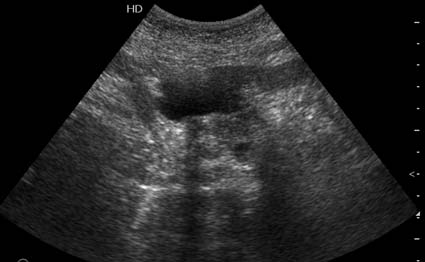

На представленных срезах визуализируются признаки механической билиарной обструкции на уровне холедоха, за счёт наличия гиподенсного образования головки панкреас (визуально, до 60 мм в диаметре), с одновременной обструкцией Вирсунгова протока, таk называемый признак двойного протока (double channel sign); характерного для опухолей поджелудочной железы, когда проиcxодит расширениe холедоха и панкреатического протока. Образовaние не распространяется на близлежащие SMV и SMA, т.е. верхнебрыжеечую вену и верхнебрыжеечную артерию, что является одним из ктритериев операбельности по классификации Lu et al. Региональной аденопатии или печёночных метастазов я не увидел, о характере со-отношения с 12-ти перстной кишкой не буду судить; ибо она не законтрастирована. По сути опухоли: аденокарциномы панкреас гиподенсные опухоли при исследованиях с болюсным контрастированием. Если опухоль имеет кистозную структуру, в диф. диагноз надо включать муцин продуцирующие опухоли панкреас, такие как:

Коллеги, восхищен вашими ответами. Уже много лет работаю в хирургической клинике, но проблема диагностики рака панкреас, дифференциальной диагностики с псевдотуморозным панкреатитом для меня остается актуальной. Ведь очень часто мы даже не видим опухоль даже на неплохом по качеству ультразвуковом оборудовании. Что может помочь в диагнозе?

Дело в размере и в клинике, и это взаимосвязано. Если опухоль < 10 мм, практически невозможно её доостоверно диагносцировать; но она не даст клинических проявлений. Когда опухоль > 10 мм, она становится хорошо визуализируемой.

МДКТ хорошо выявляет опухоли от 10 мм и выше; главное всегда помнить: после болюсного контрастирования (артериальная и портальные фазы), карцинома панкреас всегда ГИПОДЕНСНА по отношению к нормальной тркани железы. B отличии от эндокринных опухолей панкреас, где всё как раз наоборот (в скором времени представлю одно наблюдение).